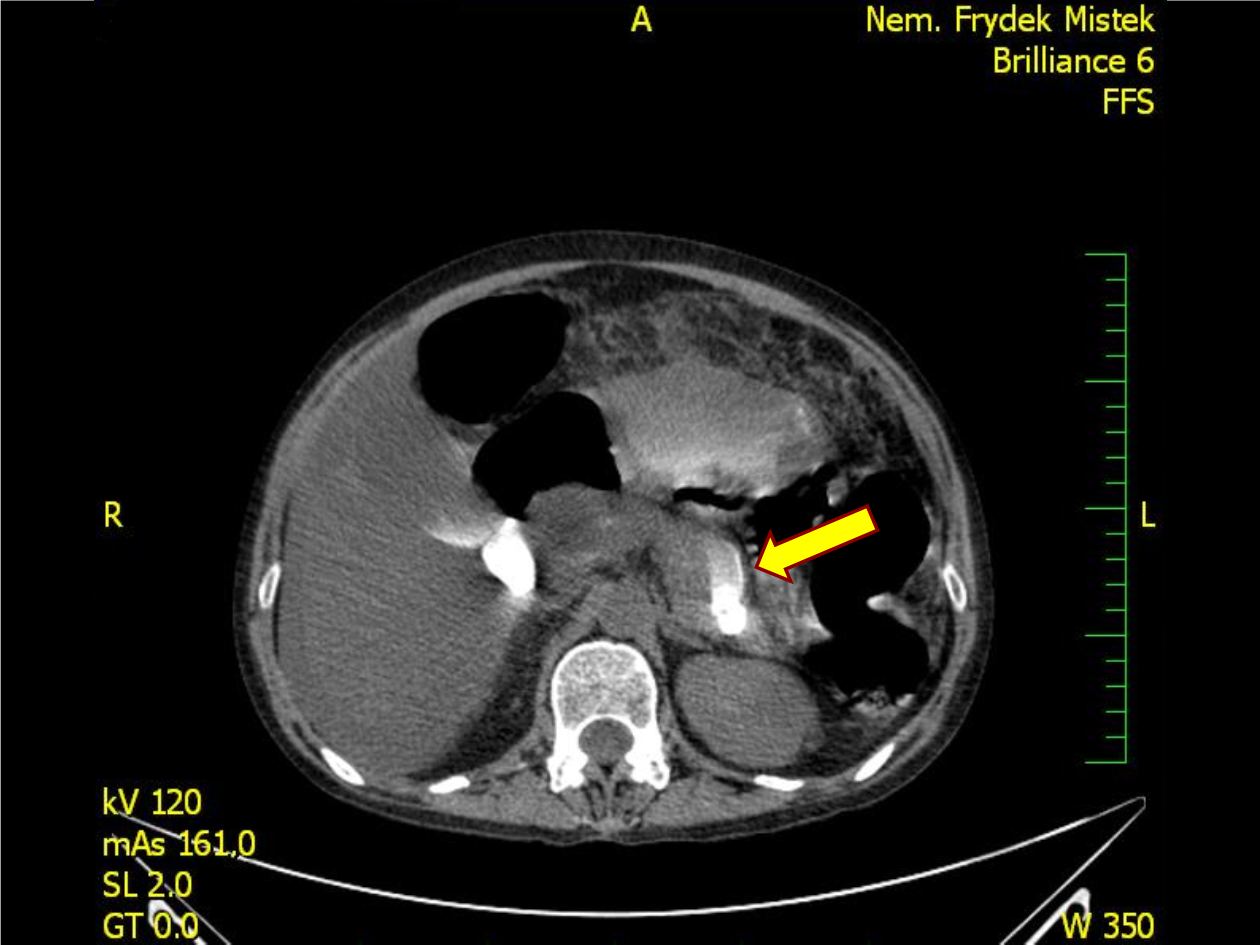

Jaterní

cirhóza s ascitem?